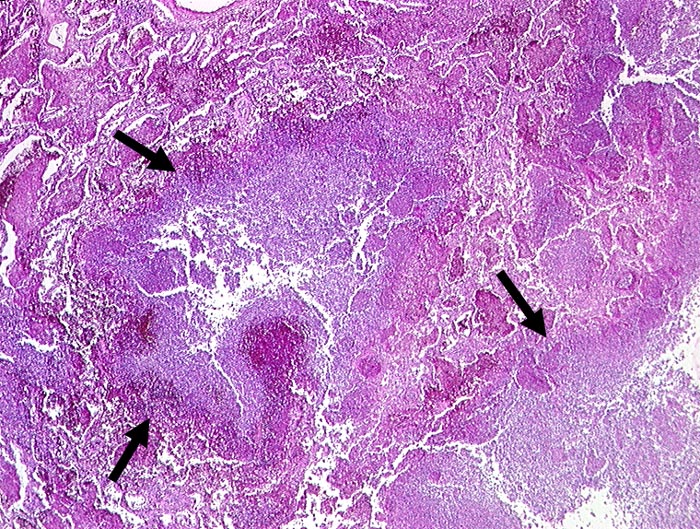

PathoPic ID 195 - abszedierende Pneumonie

abszedierende Pneumonie

Entzündung infektiös

Lunge

Im Zentrum und rechts unten im Bild zerstörtes Lungenparenchym. Anstelle des Parenchyms

eitrige Einschmelzung.

Histologie